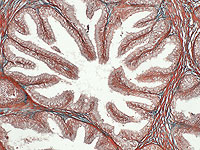

Wikipedia.org. Фото: Endolysosome

Новое исследование показало, что микроскопические частицы пластика были обнаружены у девяти из десяти мужчин с диагностированным раком предстательной железы. Причем внутри самих опухолей их оказалось больше, чем в прилегающей здоровой ткани.

В рамках исследования были проанализированы образцы ткани предстательной железы десяти пациентов, перенесших операцию по ее удалению. Частицы микропластика выявили в 90% опухолевых образцов и в 70% образцов здоровой ткани. Особенно показательно, что в раковой ткани концентрация пластика была значительно выше: в среднем примерно в 2,5 раза больше, чем в здоровых тканях – около 40 микрограммов на грамм против 16 микрограммов на грамм.